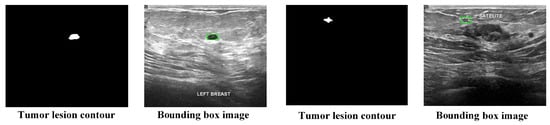

This study assesses the model on two publicly available breast ultrasound image datasets. The first dataset is the Breast Ultrasound Image (BUSI) dataset, which is a publicly available resource provided by Al-Dhabyani et al. [22]. The database contains 780 images from 600 patients, with 133 images showing normal, non-tumor tissue and the remaining 647 containing tumor images. Each image includes labeled lesion segmentation contours and lesion type. Since the BUSI dataset only provides lesion segmentation contours and lacks bounding box annotations, we generate the bounding boxes for BUSI images during data preprocessing based on the lesion segmentation contours. An example of a preprocessed image is shown in Figure 1. It is noteworthy that some images in the dataset contain two or more tumors, so when generating bounding boxes, multiple bounding box annotations are created for each image, making each bounding box an individual data sample. Table 1 presents the detailed information of the preprocessed dataset for training and testing the model.

Figure 1. Example of BUSI dataset preprocessing.